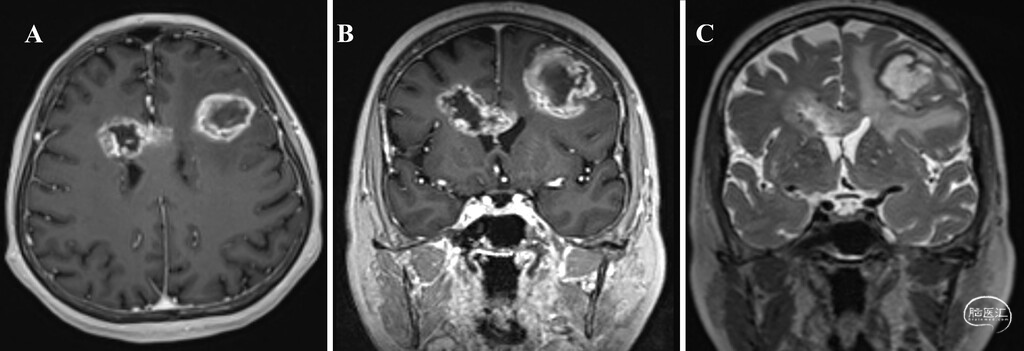

● 病例1:患者为71岁女性,因记忆力减退、言语紊乱就诊。MRI检查显示为多灶性病变,其中左侧额叶见一大小约37×33×32毫米的不均匀强化肿块,右侧脑室旁见一大小约37×28.8×25.5毫米的病灶并累及胼胝体(图1)。考虑到患者年龄及需要避免多次开颅,神经肿瘤多学科会诊建议采用同期混合手术方案:先对左侧额叶病灶进行开颅切除,随后立即对脑室旁病灶实施LITT。

图1:病例1术前MRI,示多灶性GBM。A:轴位增强T1加权像显示左侧额叶有一不均匀强化肿块,右侧脑室旁肿块延伸至胼胝体。B:冠状位增强T1加权像显示左侧额叶不均匀强化病灶伴中央坏死,右侧脑室旁肿块累及胼胝体前部。C:冠状位T2加权像显示多灶性肿块,包括累及右侧胼胝体前部及脑室旁区域的病灶,以及左侧额叶伴瘤周水肿的肿块。